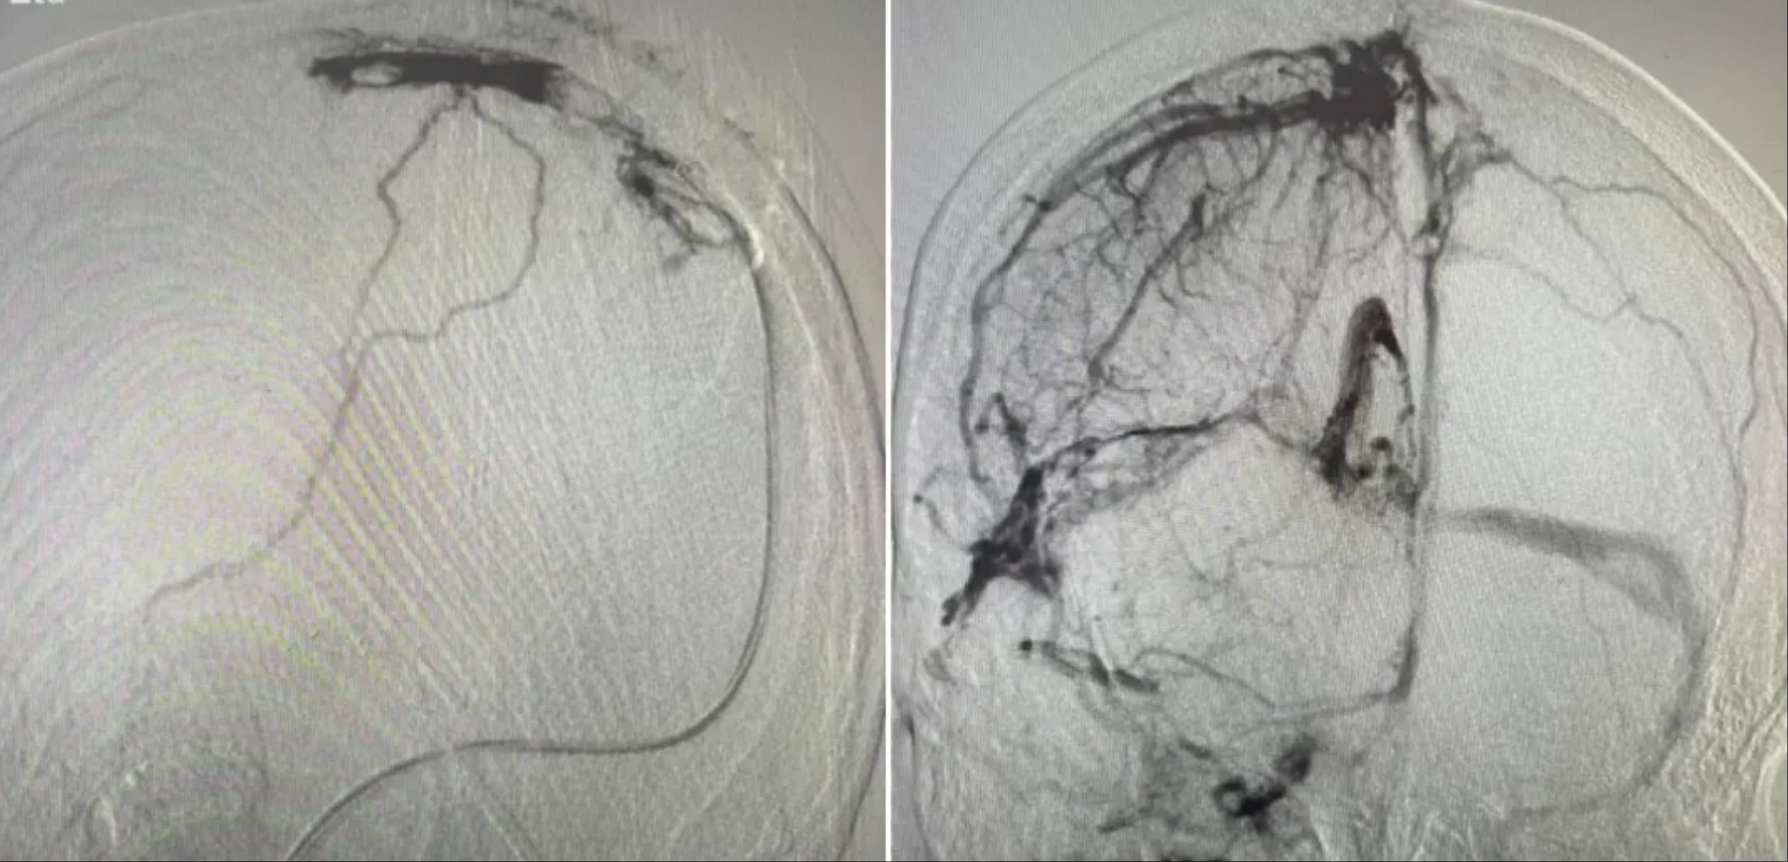

8月1日,在全麻下针灸科医疗团队为刘雯实施颅内静脉窦取栓+溶栓+球囊扩张成形术,整个手术3小时,过程顺利。术后继续予抗凝、脱水降颅压、抑酸护胃、营养支持、肢体康复及针灸等中西医综合治疗。

术前上矢状窦、横窦,乙状窦大量血栓,术后静脉窦基本通畅

术后第七天,在医疗团队和家人的鼓励下,刘雯成功地迈出了术后的第一步。“今天中午,她能用筷子自己夹饺子吃了!”刘雯父母的言语中充满了欣喜。8月13日,患者步行出院。